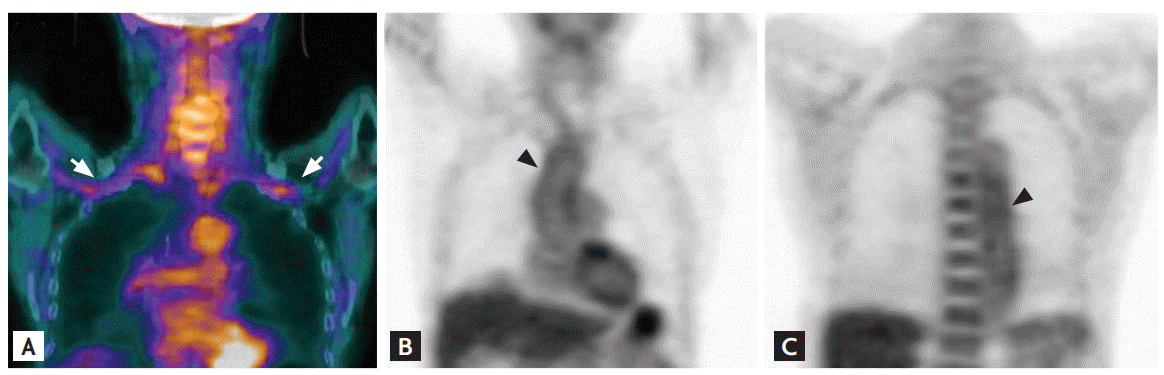

Cervical spine magnetic resonance imaging showed that both cord compression and stenosis were absent, but upper extremity angiography revealed severe stenosis of both the subclavian and axillary arteries (Fig. 1). Arteries distal to the site of stenosis, including the brachial, radial, and ulnar arteries, exhibited decreased blood flow, with the development of collateral arteries in the surrounding region. CT aortography revealed uptake by the walls of both the thoracic and abdominal aortas, suggestive of a large-vessel vasculitis such as TA. A pulmonary embolism was also accidentally found. FDG-PET/CT was performed after injection of 12.1 mCi 18F-FDG to assess the vasculitis. Linear distinct FDG uptake was evident in both the subclavian and axillary arteries (maxSUV, 2.2), and the ascending aorta and aortic arch (maxSUV, 2.1), indicating vasculitis (Fig. 2). We found no evidence of malignancy. Although she denied any symptom of dyspnea, a pulmonary embolism was found by chance. CT revealed multiple embolisms of both pulmonary arteries (Fig. 3). The anti-cardiolipin antibody immunoglobulin M (IgM) titer was 14.10 IgM phospholipid (MPL) units (normal range, < 7.0). The anti-β2 glycoprotein-1 antibody IgM titer was 22.0 U/mL (normal range, < 5), and the anti-lupus anticoagulant antibody titer was 1.91 (normal range, 0 to 1.24). The level of protein S was 54.5% (normal range, 50.8 to 116.9), the level of protein C was 173% (normal range, 70 to 148), and the level of antithrombin III was 120% (normal range, 65 to 129). On follow-up blood tests run 12 weeks later, she was positive for anti-cardiolipin antibody IgM, at 11.80 MPL units (normal range, < 7.0).

Figure 3.

(A, B) Axial images taken via computed tomography. Multiple embolisms are evident in both pulmonary arteries.